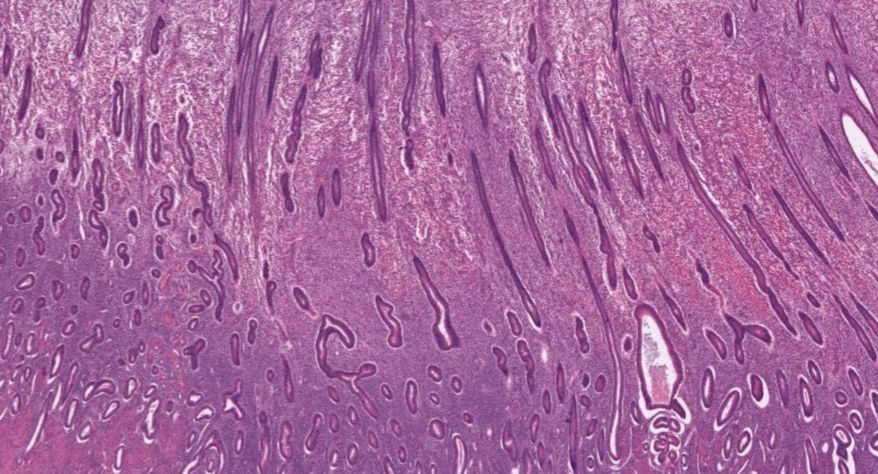

2 子宫

2.子宫内膜增生